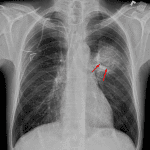

Indication: Pneumonia in immunocompromised patient

- Rounded opacity centered in the superior segment of the left lower lobe with a crescent of air noted. The opacity does not appear to displace or cross the major fissure

- No pleural effusion or pneumothorax

- Normal size and configuration of the cardiopericardial silhouette

- Angioinvasive aspergillosis

Rounded opacity centered in the superior segment of the left lower lobe with a crescent of air noted along its inferior aspect. This appearance is concerning for atypical pneumonia, in particular invasive aspergillosis. Consider chest CT for further evaluation.

- Angioinvasive subtype: nodular opacities with groundglass halos or peripheral wedge shaped areas of consolidation. Air crescent sign can be seen during the healing phase as tissue necroses and retracts